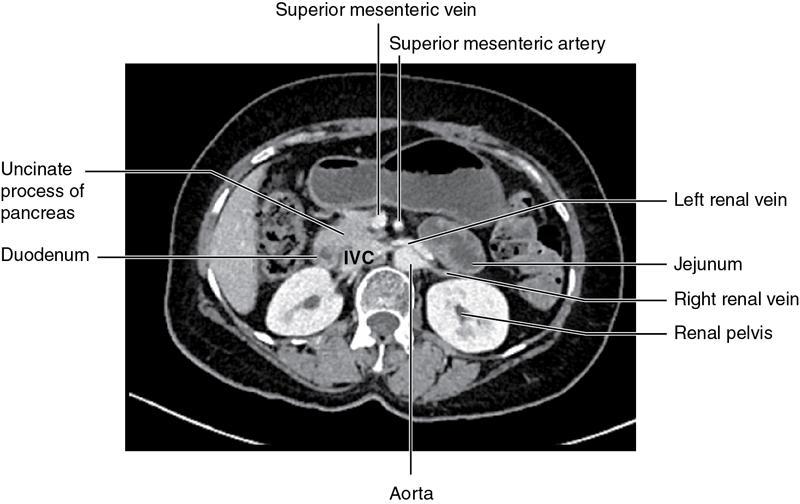

CROSS SECTIONAL ANATOMY OF ABDOMEN Satya Jha NORMAL ANATOMY OF ABDOMEN AND PELVIS Amandeep Singh The two major surfaces: The anterior and posterior layers of the coronary ligament converge on bare area (not covered by peritoneum). Its right and left margins form the right and left triangular ligaments. The right triangular ligament extends toward the diaphragm and separates right subphrenic space from right subhepatic space. The left triangular ligament gives tracts extending to the diaphragm and falciform ligament and does not compartmentalize the left subphrenic space. Ligamentum teres or the obliterated umblical vein is contained in falciform ligament which attaches the liver to anterior abdominal wall. The main portal vein, the proper hepatic artery and the common bile duct are contained within investing peritoneal folds of hepatoduodenal ligament at the porta hepatis (Fig. 7.2.2.1). Liver is divided into eight segments which are functionally independent and have their own vascular supply and biliary drainage. Arterial circulation: The branches of the hepatic artery accompanying the portal veins. Hepatic venous system: The right, middle, and left hepatic veins draining into IVC (Figs. 7.2.2.2 and 7.2.2.3). The gallbladder is a blind pear-shaped muscular membranous sac which is an embryologic derivative of the foregut, is a pouch lying along the undersurface of the liver. The gallbladder fossa is located in the plane of the interlobar fissure, which lies between the right and left hepatic lobes. Its major function is to store and concentrate bile which is produced by the liver. It measures approximately 4 cm in diameter when it is normally distended. Gallbladder is a smaller tubular structure in contracted state. The normal gallbladder wall thickness ranges from 1 to 3 mm. The gallbladder is divided into the fundus, body and neck. Infundibulum is present in the region of neck of the gallbladder, which is called the Hartmann pouch, where gallstones are usually impacted. Intrahepatic biliary radicles (IHBRs) scattered throughout the liver get confluent towards the hilum. They unite to form the right and left main hepatic ducts which further unite to form common hepatic duct (CHD) at the hilum. Common bile duct is formed by the union of cystic duct with common hepatic duct. The main pancreatic duct is joined with the common bile duct to form the ampulla of Vater at the major duodenal papilla (Figs. 7.2.2.4 and 7.2.2.5). Pancreas is located in anterior pararenal space of retroperitoneum anterior to perirenal (Gerota’s) fascia and posterior to parietal peritoneum. It is divided into head, uncinate process, neck, body and tail from right to left. Pancreas lies anterior to portal vein, which marks the point of transition between the body and neck. The region between head of pancreas and second and third parts of duodenum is known as the pancreatic groove. In postnephrectomy cases or with agenesis of kidney or ectopic kidney, pancreas moves posteriorly to partially fill in the empty renal fossa; its soft tissue density should not be mistaken for recurrent tumour. It is located in the pancreatic groove and is bounded superiorly by the duodenal bulb, laterally by second portion of duodenum, inferiorly by third portion of duodenum, medially by superior mesenteric vein and anterior to inferior vena cava. It is a wedge or wedge shaped lying posterior to superior mesenteric artery and vein. It is an imaginary junction between the head and body and lies directly over the junction of the splenic vein and superior mesenteric vein. It is located posterior to the lesser sac and anterior to the aorta, left adrenal gland, left kidney, and renal vessels and runs obliquely upward to the left of the superior mesenteric vessels. It is situated median to the colonic flexure and anterior to the left kidney. It is located in close proximity to the splenic hilum without a notable relation with the body of pancreas. It is seen anterior to the left kidney and median to the colonic flexure. The distal part of the tail passes between the peritoneal layers of the splenorenal ligament (Fig. 7.2.2.6 and 7.2.2.7).